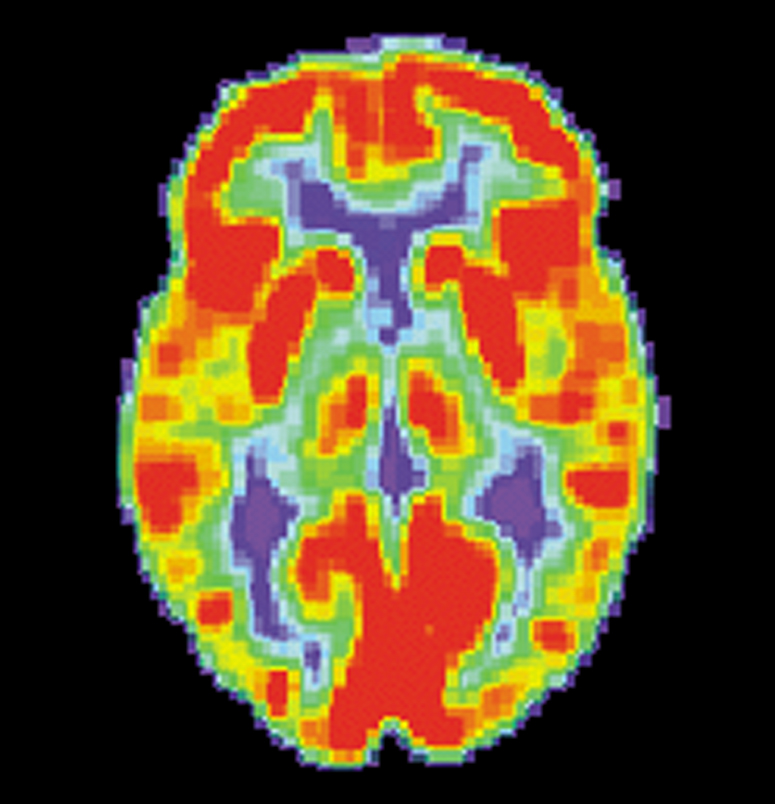

“In fact, brain imaging studies show that the experience of physical pain and the experience of relational pain, like rejection, look very similar in terms of location of brain activity.”